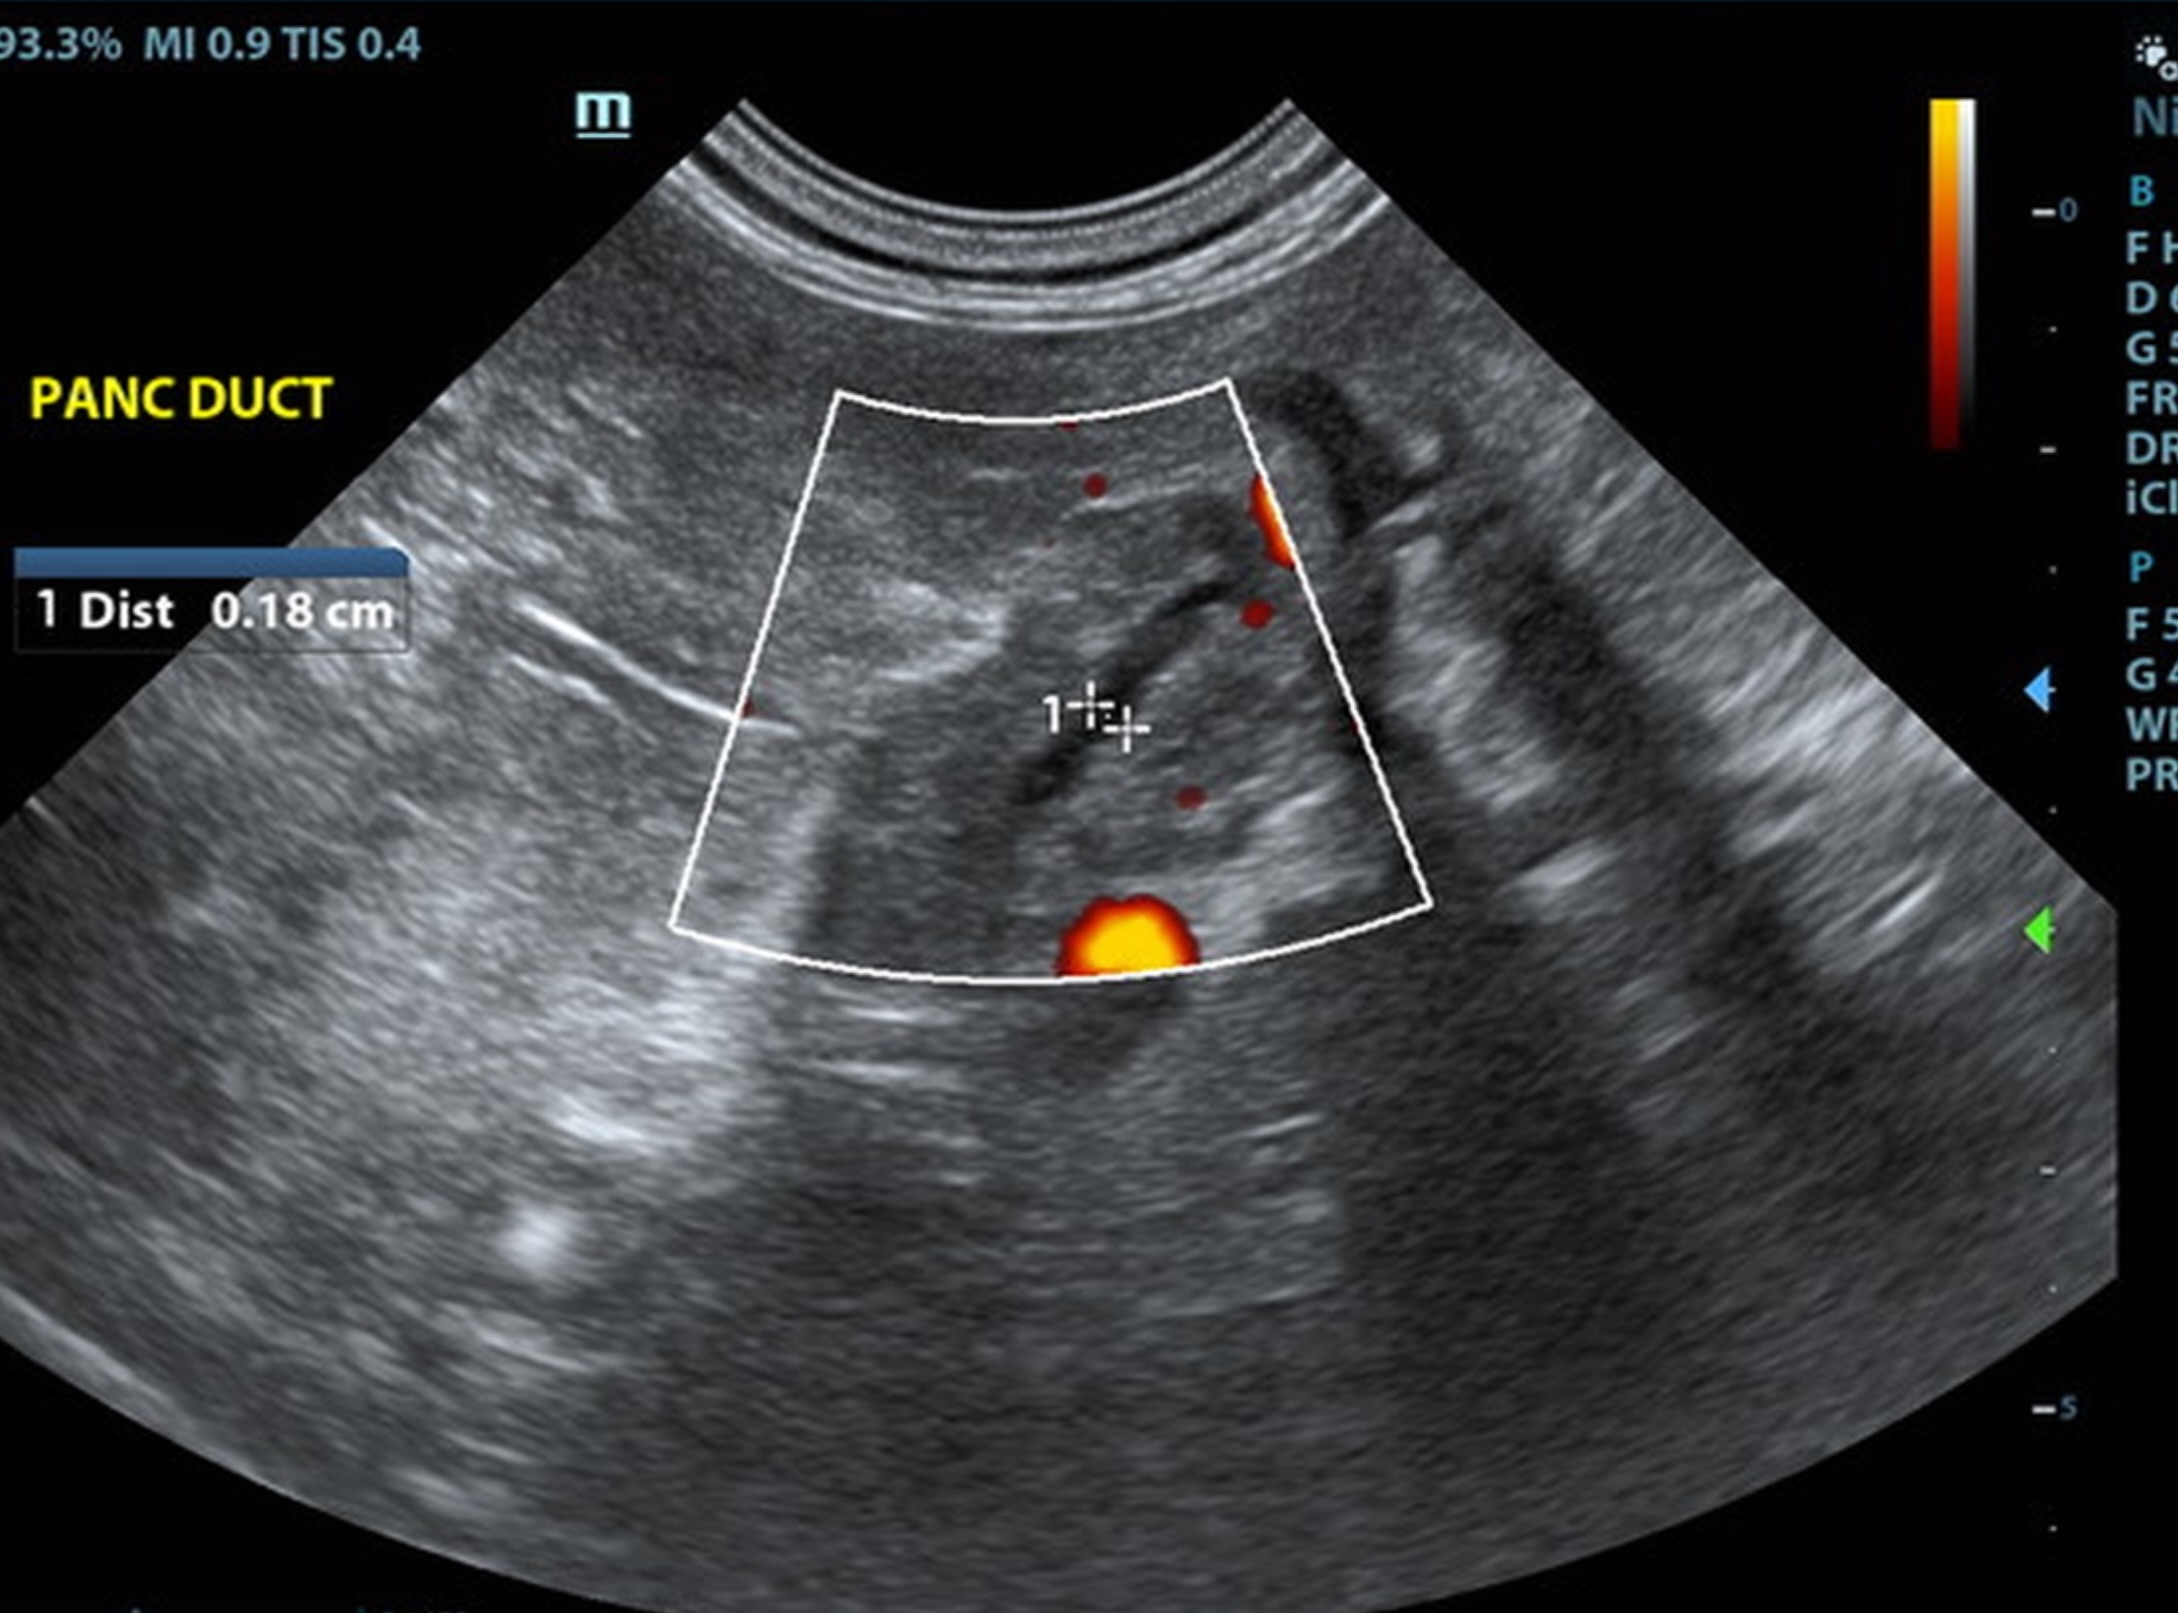

The pancreas revealed coarse architectre and dilated pancreated duct. Coarse, irregular contour noted. The left limb of th pancreas was irregular with increased pericapsular inflammator pattern.